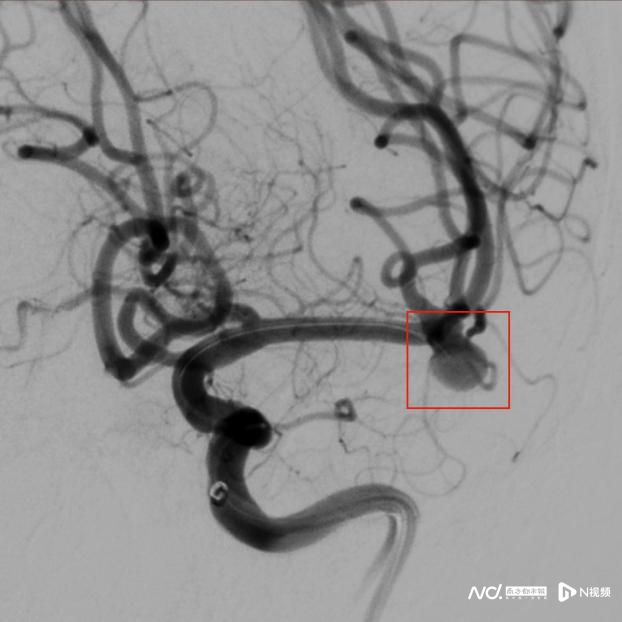

栓塞前的脑血管分叉处的动脉瘤

59岁文女士(假名)因片刻左手麻痹、头晕前去惠州当地病院视察,末端深入,左侧大脑中动脉凹凸干接壤处长有一个动脉瘤。

大夫告诉她,这个动脉瘤位于血管分叉接壤处,剖解结构与血流能源学复杂,给与旧例的支架援手弹簧圈栓塞手术,不仅手术期间长、难度大,术中离散及造成血栓的风险更高,术后复发率也较着高于庸俗动脉瘤。